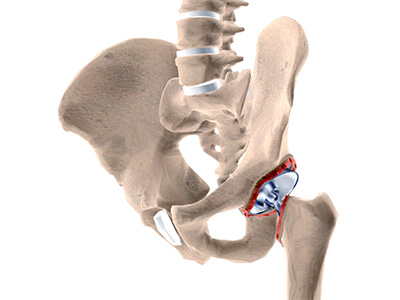

The hip joint is the junction where the hip joins the leg to the trunk of the body. It is comprised of two bones: the thigh bone or femur and the pelvis which is made up of three bones called ilium, ischium, and pubis. The ball of the hip joint is made by the femoral head while the socket is formed by the acetabulum. The Acetabulum is a deep, circular socket formed on the outer edge of the pelvis by the union of three bones: ilium, ischium, and pubis. The lower part of the ilium is attached by the pubis while the ischium is considerably behind the pubis. The stability of the hip is provided by the joint capsule or acetabulum and the muscles and ligaments which surround and support the hip joint.

The head of the femur rotates and glides within the acetabulum. A fibrocartilagenous lining called the labrum is attached to the acetabulum and further increases the depth of the socket.

- Acetabular labrum: The labrum is a fibrous cartilage ring which lines the acetabular socket. It deepens the cavity, increasing the stability and strength of the hip joint.